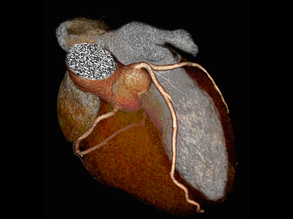

Squeezing the Heart

Inflaming Hearts